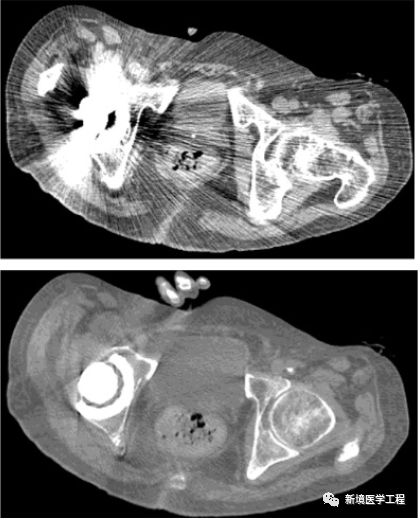

2.3「体内金属伪影」

【产生原因】

患者体内有金属,因为金属吸收了X射线,导致投影数据产生不完全,部分数据丢失导致放射状伪影。

【解决办法】

-

移除金属物体(如可行)

-

使用去金属伪影的算法,如MAC等

2.6「体外金属伪影」

【产生原因】

体外的金属未去除,密度较大产生伪影。

【解决方法】

去除金属,再次